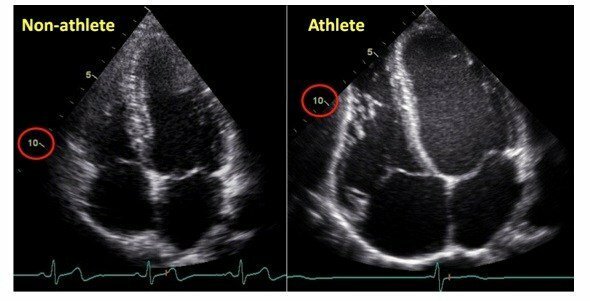

Corazón de atleta

Los cardiológos Reindell, Roskman y Keull , hablaron del efecto verdadero del IT, que estaba en las pausas y no durante el esfuerzo, también hablaron de no copiar de otros métodos, aportaron conclusiones sobre es aspecto normal o fisiológicos del corazón de atleta.